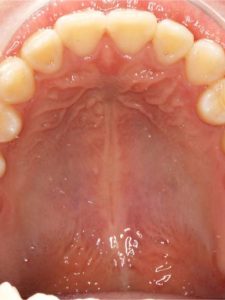

Jaw Repositioning (Orthognathic) Surgery

Before and After Images